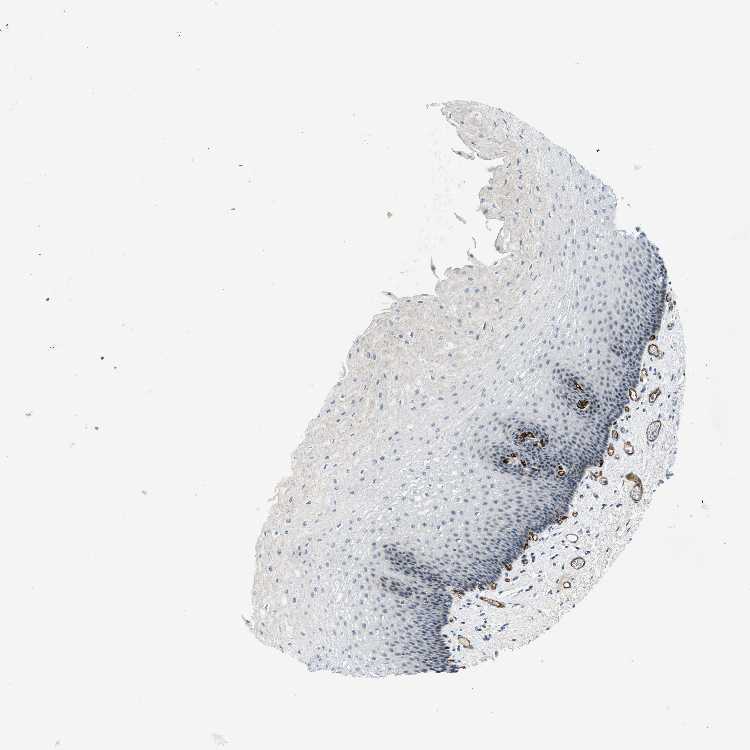

ESOPHAGUS - Antibody stainingi

Antibody staining in the annotated cell types in the current human tissue is reported as not detected, low, medium, or high, based on conventional immunohistochemistry profiling in selected tissues. This score is based on the combination of the staining intensity and fraction of stained cells.

Each image is clickable and will lead to virtual microscopy that enables deeper exploration of all samples and also displays staining intensity scores, fraction scores and subcellular localization as well as patient and tissue information for each sample.

Antibody HPA013742

Squamous epithelial cells Not detected